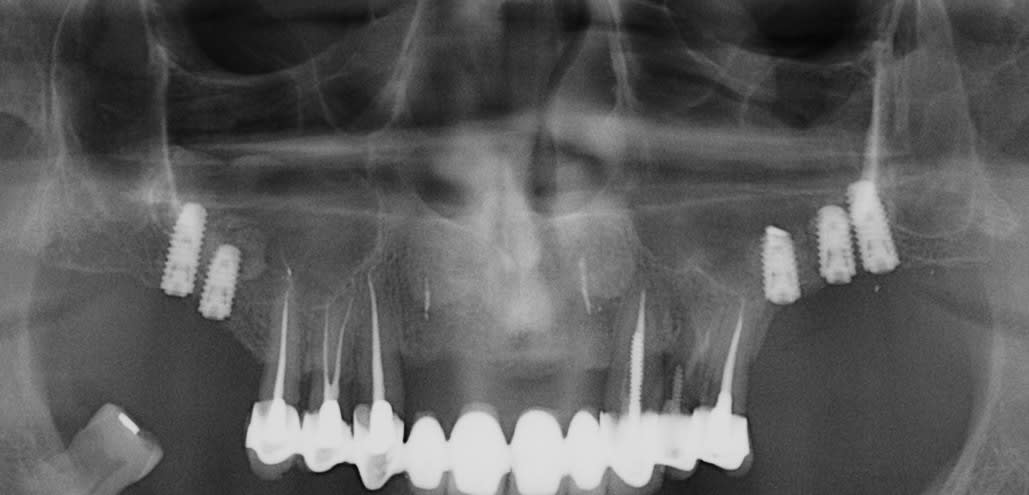

après avoir longtemps (depuis 1989) pratiqué des fenêtres latérales, je ne fais pratiquement que des summers (exemple ci dessous) en laissant du temps à la cicatrisation et jusqu'à présent pas de soucis particulier, et avant d'aller "bricoler" dans un sinus pour retirer du biooss (que je n'aime pas du tout) et/ou du tissus de "granulation", je prends le temps, et si l'implant est stable je ne me pose pas de question.

Ceci étant libre à chacun de pratiquer autrement

et comme tu peux le constater rien de "magique" ni dans la chir, ni pour la prothèse, très "bof" mais pas de problèmes pour le moment.